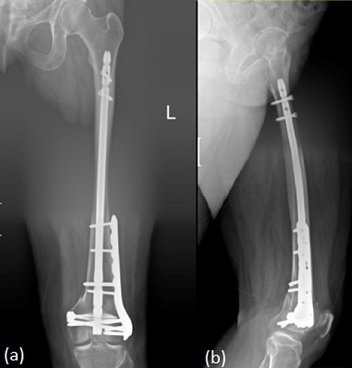

A third option is dual fixation through a nail-plate construct (Figure 3). This is gaining traction for complex AO-33C fractures, severe osteopenia, prior plate non-union, bicondylar/transcondylar patterns and select periprosthetic cases. By combining a retrograde IM nail with lateral plating or dual plating, these hybrid constructs enhance rotational axial stability, reduce non-union risk, and permit earlier, safer weight bearing. Contemporary reviews and case series detail evolving indications and surgical techniques.

Radiograph of a left combined femoral intramedullary nail and plate fixation. (a) Anterior view. (b) Lateral ViewFigure 3: Radiograph of a left combined femoral intramedullary nail and plate fixation. (a) Anterior view. (b) Lateral View [20].